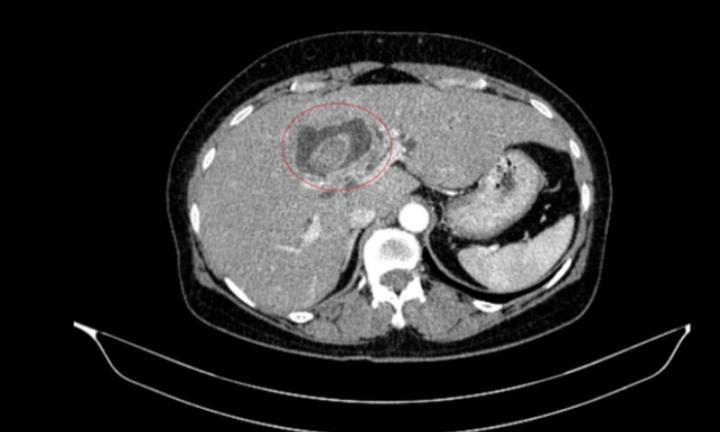

Khối u thận lộ diện sau lần khám sức khoẻ định kỳ

Những dấu hiệu âm thầm của ung thư thận dễ bị bỏ qua